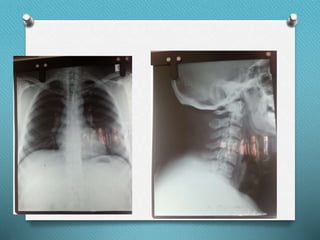

RAD

Airway O Normal Dentition/Patent nares O Mouth opening – 3 fingers breadth O TMD – >6 cm O TMJ – free/mobile O Neck mobility – slightly restricted due to surascapular hump O MP – II grade, tonsillar enlargement +Ve (?Grade IV) O Thick neck O Suprascapular hump